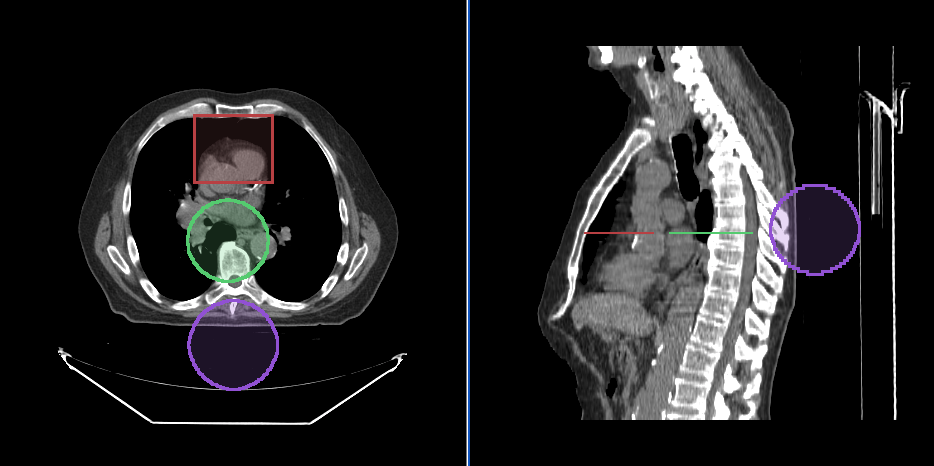

Below, you can see a screenshot of the annotation tools that are available in Cornerstone3DTools.

Segmentation Tools

Cornerstone3D also provides segmentation tools. This includes 3D SegmentationDisplay

and 3D segmentation editing tools such as brush, rectangle and circle scissors, and

3d sphere tools.